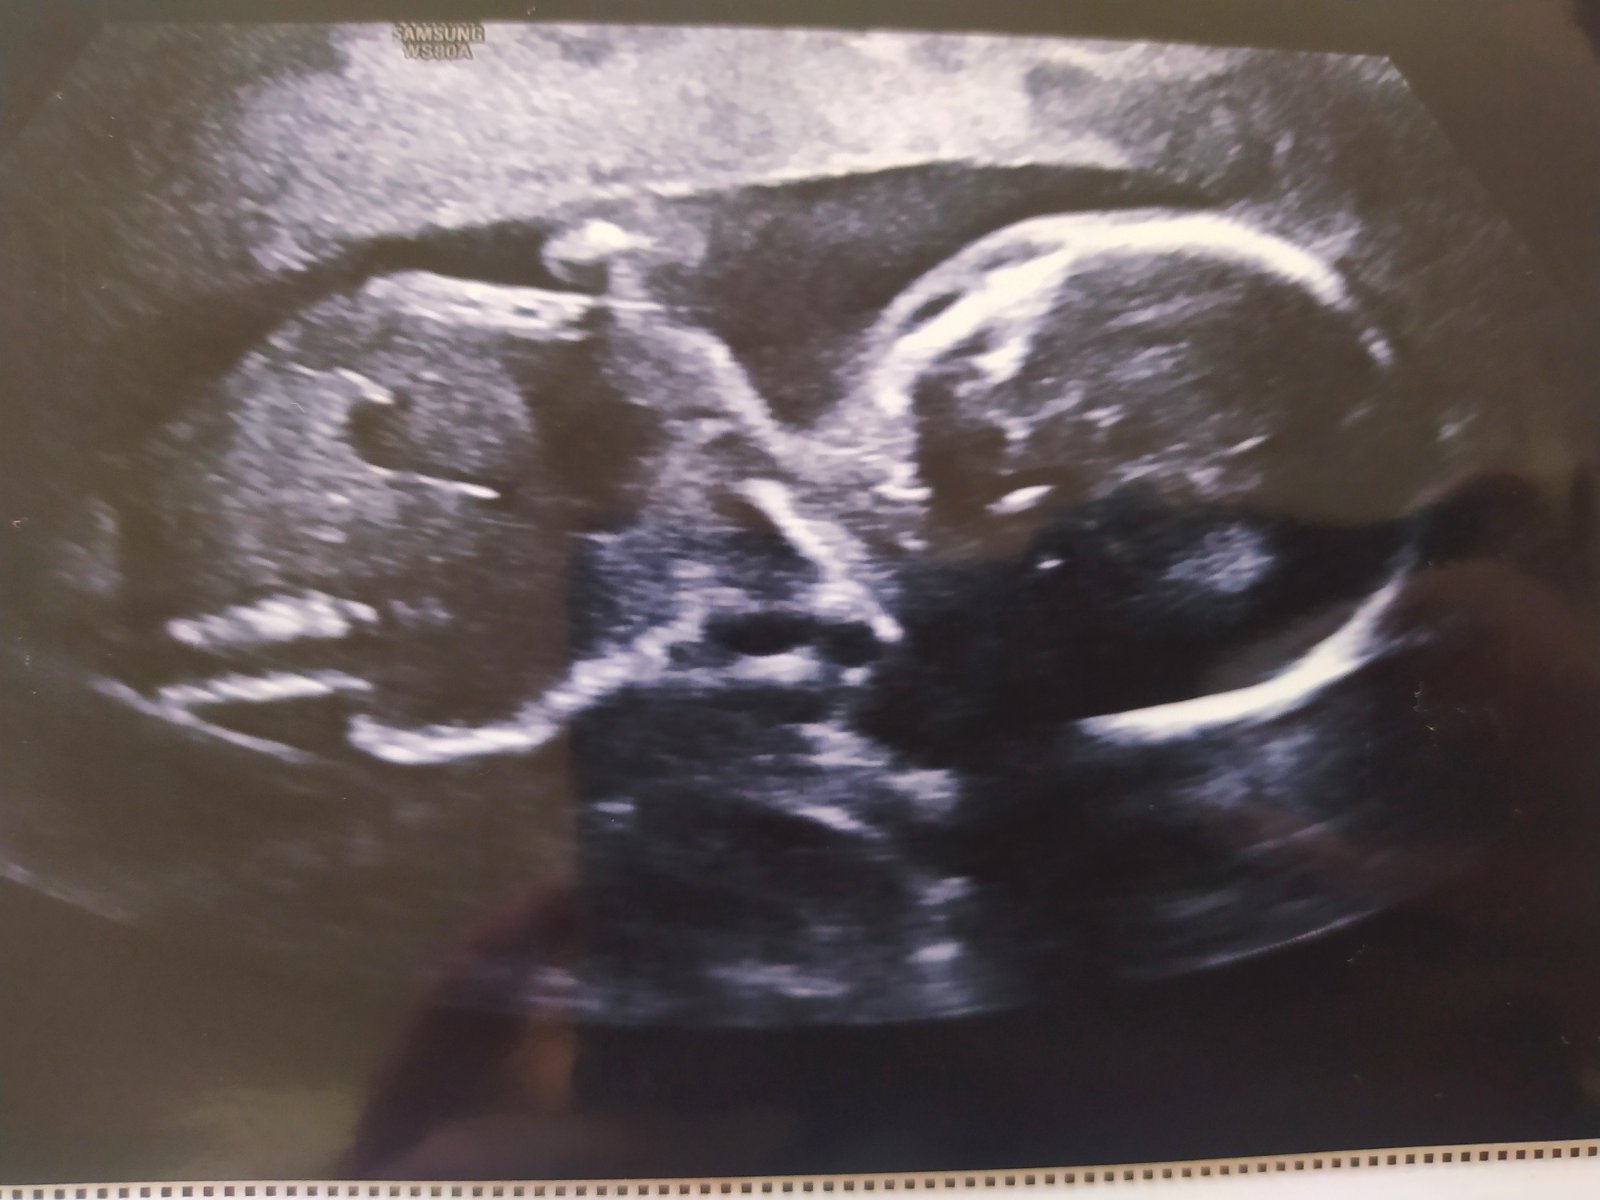

Ahoj 😀

Přelom 24. a 25.tt jsem objednaná na 3D,4D ultrazvuk... Je to dárek hlavně pro manžela, který se od první chvíle neuvěřitelně moc těší, že uvidí mimi na utz a kvůli corona době 🥴 ho se mnou na žádný nepustili a jeho to mrzí.. Tak jsem nás objednala do České Třebové za 1400,-, což je celkem pálka 😅, ale pustí ho tam 100% 😁. Akorát se trochu bojím, že z toho bude velký prd, protože malá je na každým utz. otočená tak, že vystrkuje prdel 😂 (viz. poslední fotka) + mám placentu na přední straně 😶 ...ale zase je poslední dobou v břichu celodenně akční, tak nevím 😁